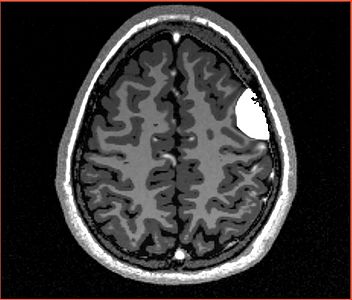

NOTE: red outlines the boundary of the label corresponding to the initial tumor seed!

All the following experiments are based on the "thin dura" input labels, and the tumor seed image shown on the right. The tumor label is shown in green color. Note that the tumor is touching the gray matter label.

The following screenshots capture the same axial slice (#119) of the following images in order: (1) image containing the tumor probabilities, and (2) the simulated Gad enhanced image, both overlayed with the warped tumor/brain tissues labels.

Poisson ratio 0.5

(initial value)

Note very very minimal deformation of the surrounding brain tissue, although the tumor volume increased, for Poisson=0.5.